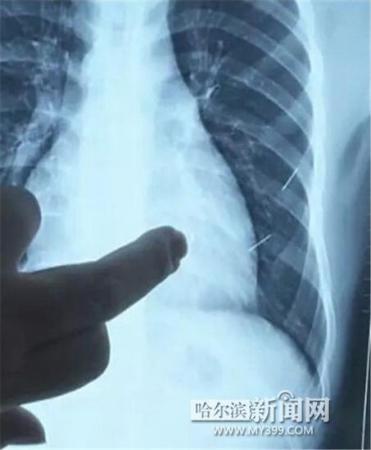

醫(yī)生指出X光片上的針狀物

昨日上午,記者在哈醫(yī)大二院第八住院部心外三病房找到了躺在病床上痛苦不堪的董立仁,家屬正在他身旁不斷安慰著他。見記者前來,董立仁母親李百燕拿出一張X光片,上面可以清晰地看到胸腔內(nèi)一共有4根針狀物,其中一根在心臟部位,兩根在胸腔壁上,還有一根在腹腔壁上。

昨天16時(shí)30分左右取針手術(shù)開始。因鋼針隨時(shí)會(huì)危及患者生命,此次手術(shù)定義為大型手術(shù)。開胸后,醫(yī)生打開董立仁心包,發(fā)現(xiàn)一枚鋼針已深深扎入心臟,僅露出1厘米長(zhǎng)度在外。拔出鋼針后,醫(yī)生發(fā)現(xiàn),這枚針長(zhǎng)達(dá)5厘米。受鋼針影響,心包出現(xiàn)大量積液,近800毫升。

隨后,在下胸壁位置,第二枚鋼針順利取出。在尋找另兩枚鋼針過程中,普外、胸外多名醫(yī)生也參與手術(shù),為主刀醫(yī)生提供更為穩(wěn)妥的處理建議。根據(jù)X光片顯示位置,醫(yī)生未在患者體內(nèi)找到剩余兩枚鋼針。醫(yī)生懷疑,其中一枚鋼針可能深藏在肋骨骨膜位置,無法尋找,最后決定結(jié)束手術(shù),做進(jìn)一步觀察,研究下一次手術(shù)方案。